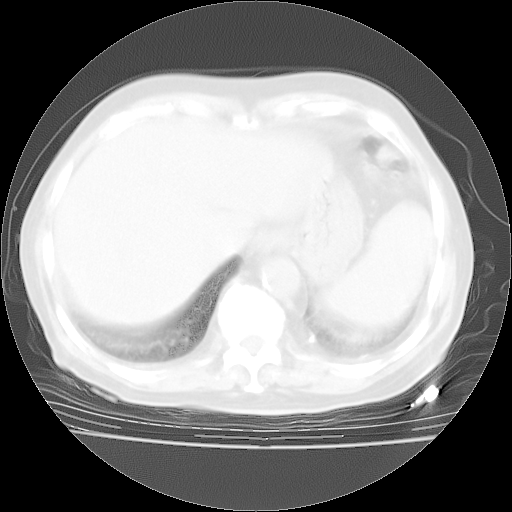

4月28日肺部CT——再次出现类似去年5月9日——透光度降低,“间质性”改变。

1、108#的是4月14日的胸部CT(发此贴时还没看着28日的CT)。14日的胸部CT其实已经出现改变(如108#所述),个人认为28日的胸部CT除纵膈窗疑似有双侧胸膜增厚或少量胸积液(可行胸部B超明确)外,与4月14日对照病变有所加重;2、已经给予“异烟肼、利福平、乙胺丁醇”抗痨治疗?如果是,甲强龙80mg可缓慢减量;如果环磷酰胺已停用,暂不使用;3、中性粒细胞92%,明显升高,目前体温情况?注意合并细菌感染可能,使用左氧氟沙星情况下,是否联用B-内酰胺类抗菌药物?另外是查免疫全套非风湿全套。

今请临免主任会诊后认为:4月14日胸部CT已有双下肺间质性改变。患者病情复发多系激素减量过快不正规所致。目前甲强龙80mg/日,一周后酌情开始减量,不易过快。环磷酰胺若已停用,暂不使用。他同意目前抗菌药物使用,但应考虑是否加用B-内酰胺类抗菌药物(中性细胞明显增高);2、结核复发目前依据不足;3、若免疫全套各项指标正常,考虑多系特发性肺间质炎可能大。4、加强支持,并注意保护胃黏膜。